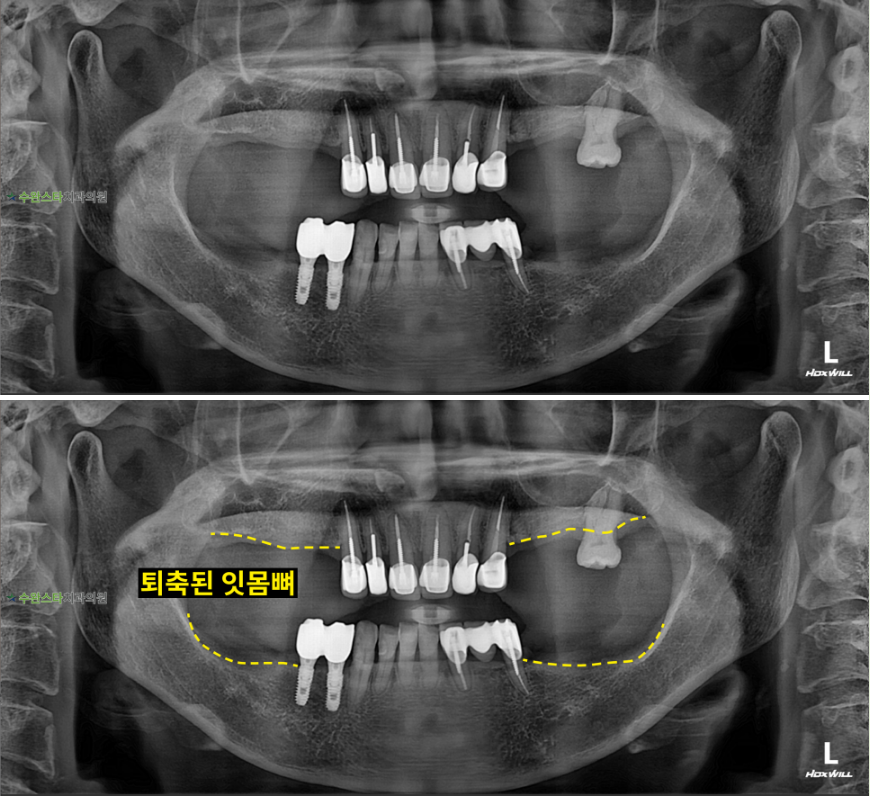

내원 시 파노라마

처음 내원 시 파노라마, 60대 여성 (2025. 12 촬영)

내원 시 파노라마 사진입니다.

살릴 수 있는 자연치아를

최대한 보존하고

발치 후 뼈 이식과

임플란트를 진행하기로

했습니다.